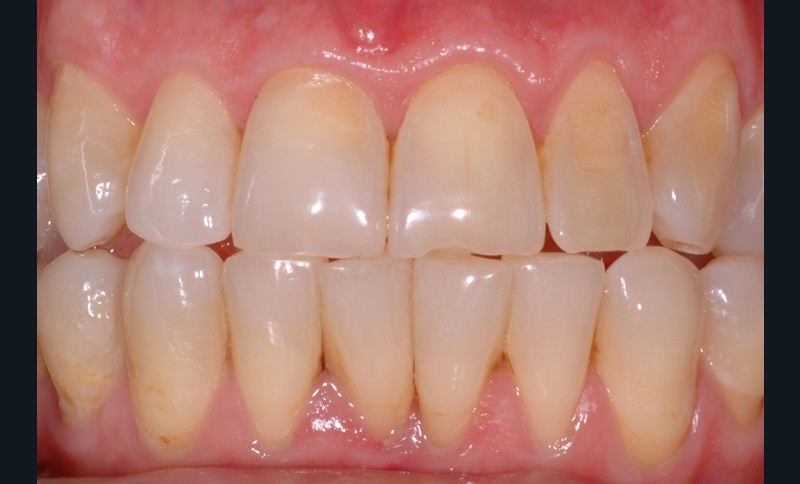

L’érosion survient lorsqu’une attaque chimique (solution acide, chélatant) rompt les liaisons intermoléculaires des tissus dentaires, potentialisant les différents autres modes d’usure mécanique (attrition, abrasion, abfraction) (fig. 5). L’aspect clinique des lésions érosives est polymorphe, mais, d’une manière générale, les surfaces sont lisses, en forme de cupules sur les sommets cuspidiens (fig. 6), de couleur satinée à terne. Les restaurations non affectées par l’environnement corrosif (amalgames, composites, alliages métalliques) surplombent généralement les surfaces amélaires et dentinaires adjacentes, alors que la morphologie dentaire est affectée. Les faces vestibulaires (fig. 7) et palatines (fig. 8) peuvent également présenter des lésions plus ou moins importantes, selon l’origine et le temps d’application de la source acide qui peut être d’origine extrinsèque (sodas, aliments acides) ou intrinsèque (sucs gastriques).